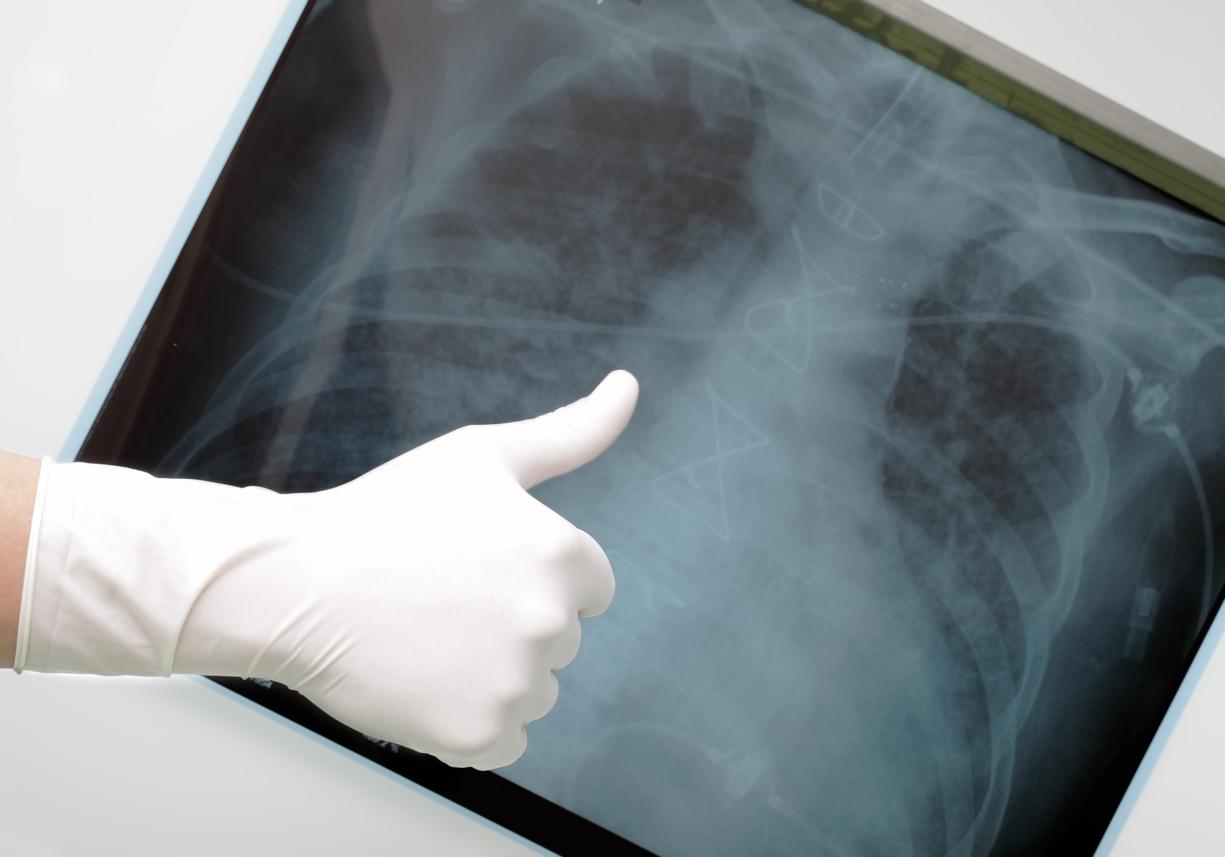

Une étude, dont les résultats sont parus en mars 2025, dans la revue Respiratory Medicine Research, a cherché à évaluer l’efficacité et l’innocuité de l’association d’un talcage pleural par thoracoscopie médicale et la mise en place d’un drain thoracique à demeure (cathéter pleural tunnelisé) dans le même temps opératoire chez des patients présentant un épanchement pleural malins récidivants. Il s’agit d’une étude française de faisabilité au cours de laquelle 25 patients atteints d’épanchement pleural malin récidivant ont bénéficié de cette prise en charge en utilisant la même porte d’entrée thoracique.. Les auteurs ont ensuite analysé les données démographiques, la durée de séjour à l’hôpital, les complications directement liées à la procédure, la qualité de vie des patients, la qualité de la symphyse pleurale et l’efficacité sur la durée du drainage. Les patients ont été suivis sur une durée de 6 mois.

Philippe ASTOUL souligne que les résultats de ce travail ont montré que la combinaison du cathéter pleural tunnelisé et du talcage permettait de raccourcir la durée d’hospitalisation et la durée de drainage à domicile. Ceci est réalisé lors d’une thoracoscopie médicale, qui permet de plus d’explorer de façon rigoureuse la cavité pleurale, de réaliser des biopsies pleurales de bonne qualité. Le talcage est réalisé puis le drain est posé via le même orifice. Le patient ne reste alors que 24 heures en hospitalisation. Il insiste donc sur l’efficacité de ce geste combiné qui diminue le risque de récidive, permet une évaluation pleurale de bonne qualité, raccourcit la durée de drainage, diminue le risque infectieux et donc améliore le confort du patient. Philippe ASTOUL émet simplement la remarque que la perception d’un corps étranger thoracique est différente selon les pays, et qu’il serait judicieux d’évaluer cette question en fonction des approches culturelles par de nouvelles études.